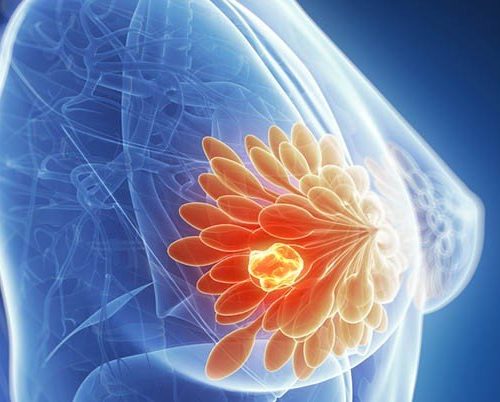

Atenção à saúde óssea

Alguns tratamentos utilizados para combater o câncer de mama podem levar a perda de massa óssea. Soma-se a isso o fato de que as mulheres…